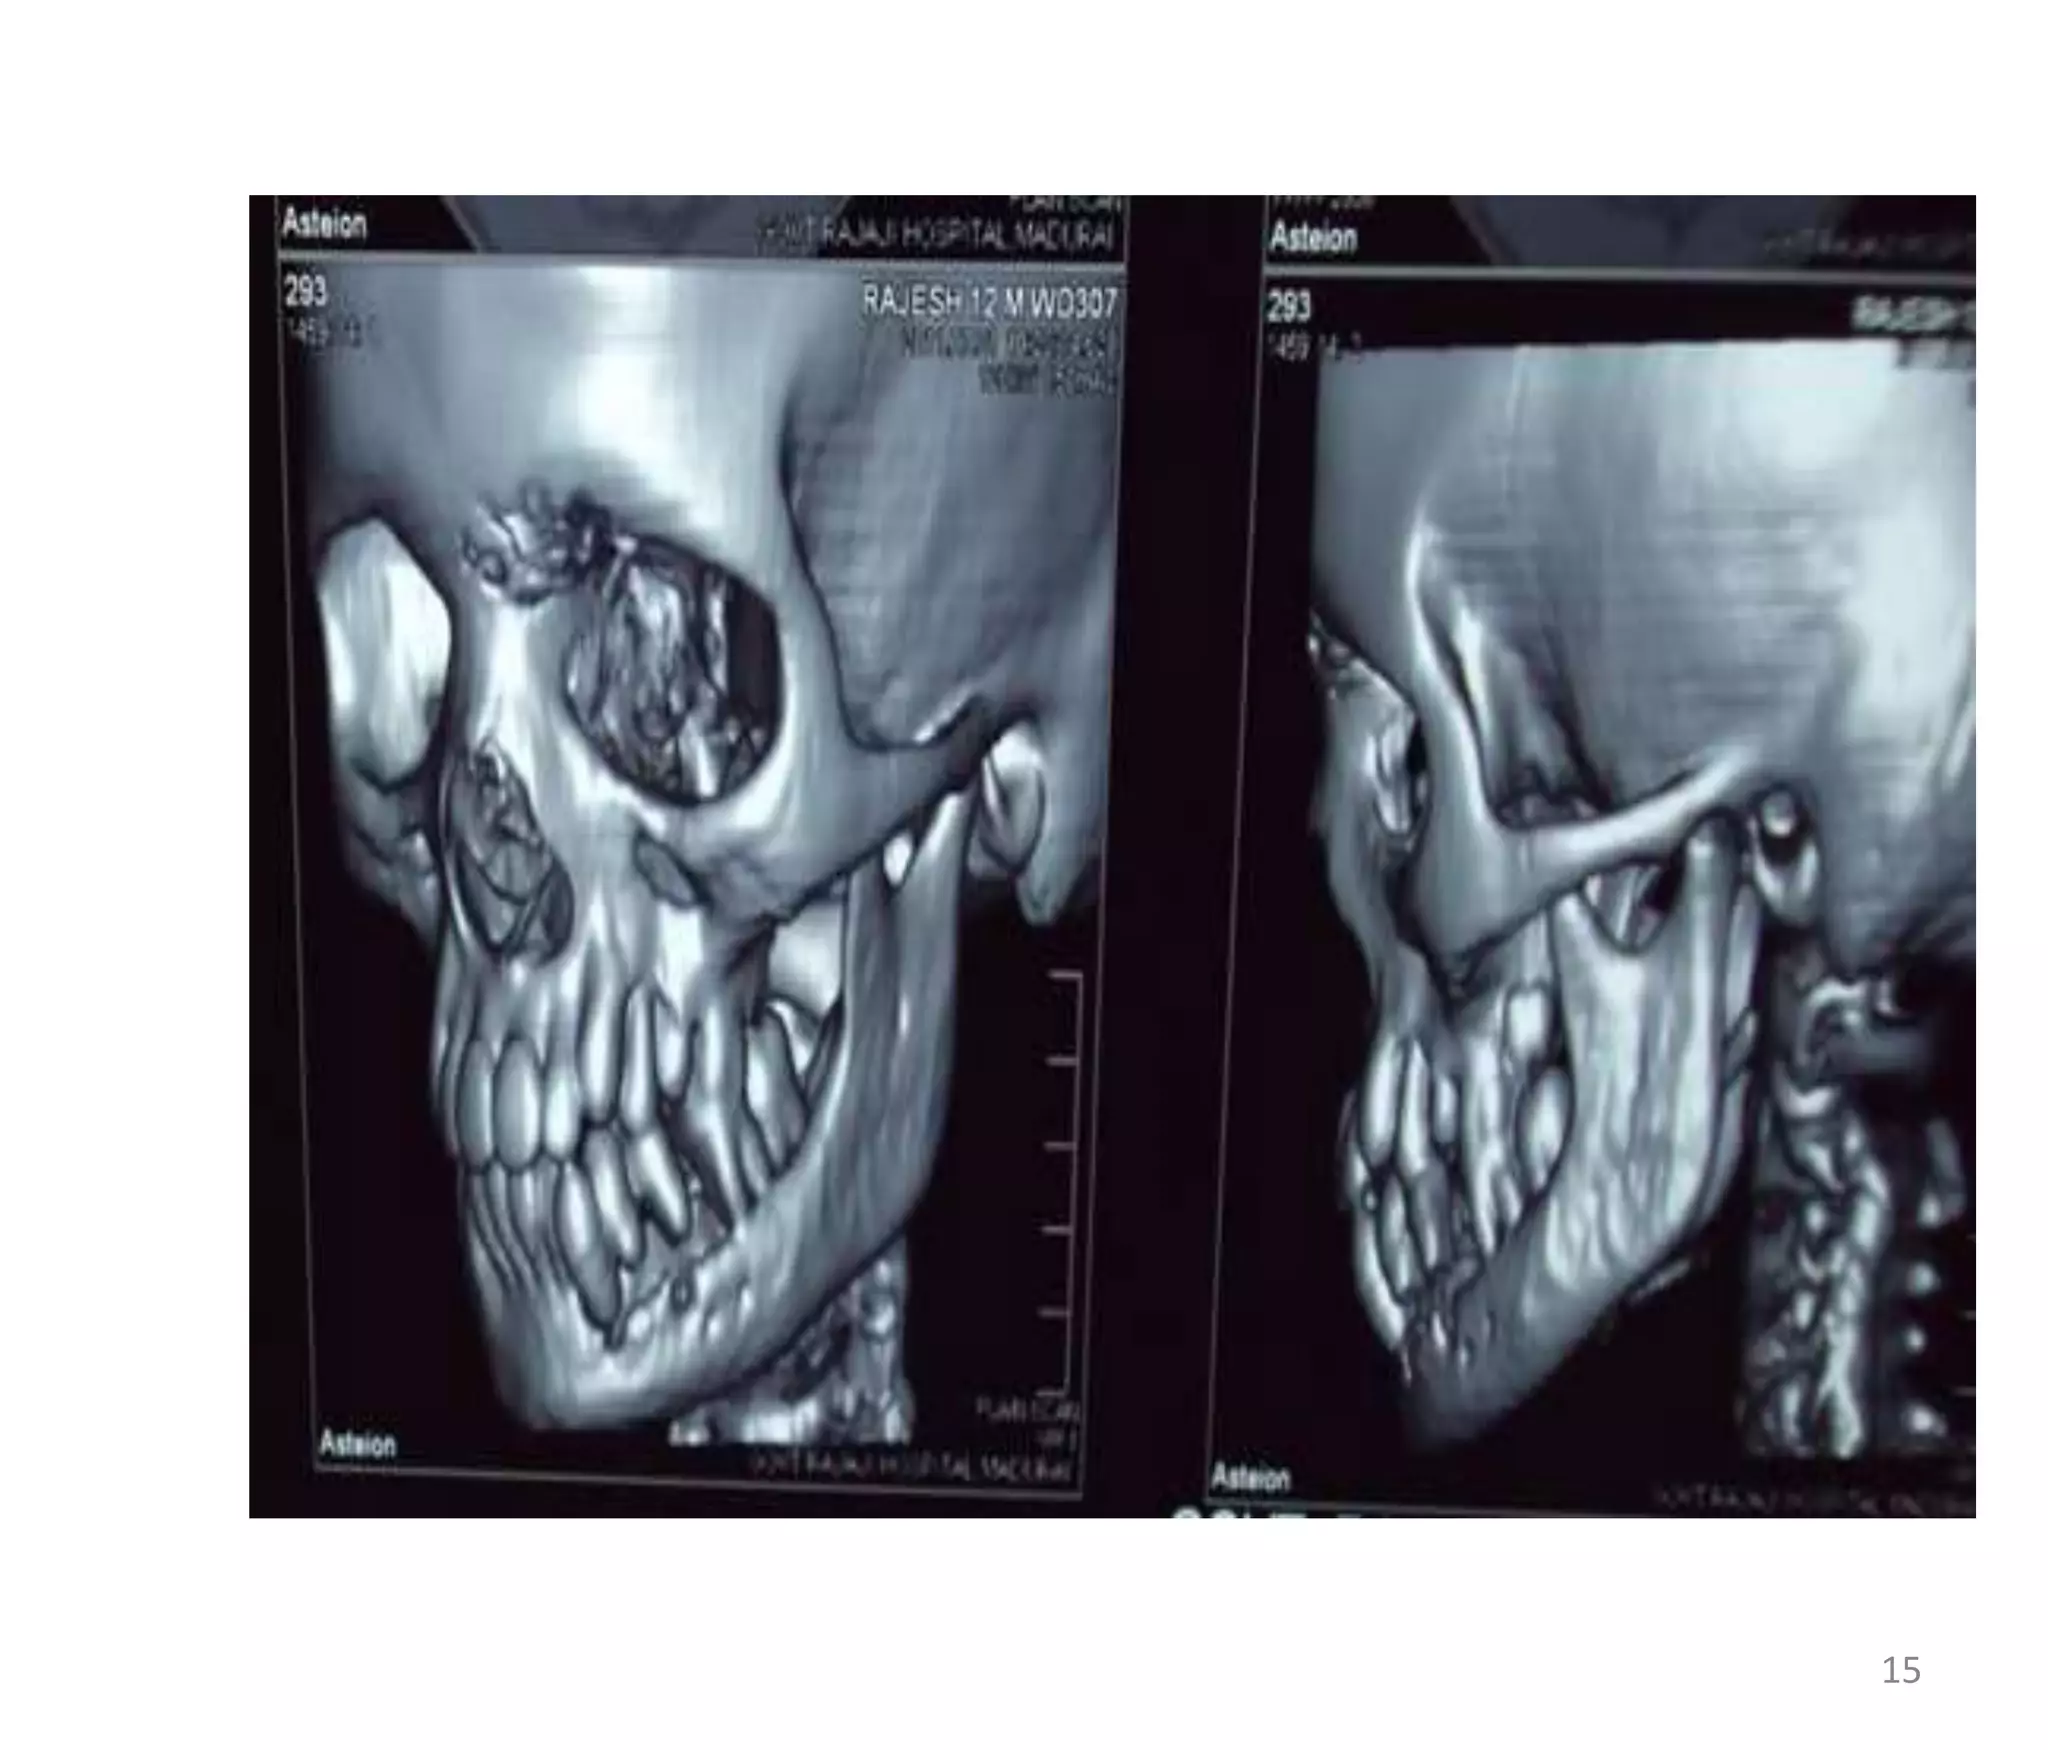

CT - CONTRAST

 Moderate heterogenous enchancement.

14

15

CT - CONTRAST Moderate heterogenous enchancement. 14

• 15.